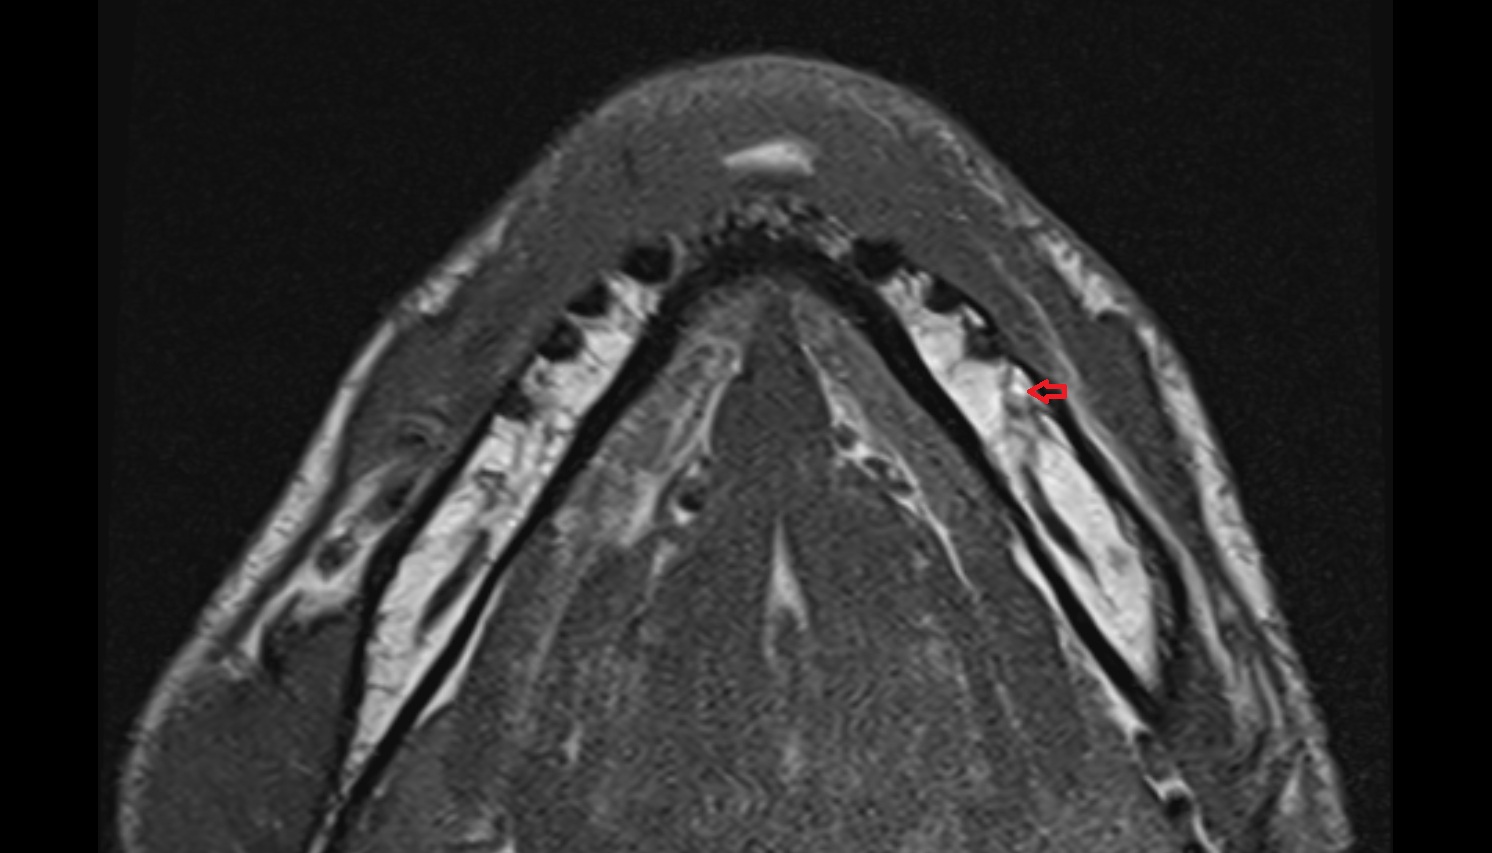

- Temporomandibular joint

- Mandibular condyle

- Mandibular fossa

- Lateral pterygoid muscle

- Masseter muscle

- Medial pterygoid muscle

- Temporalis muscle